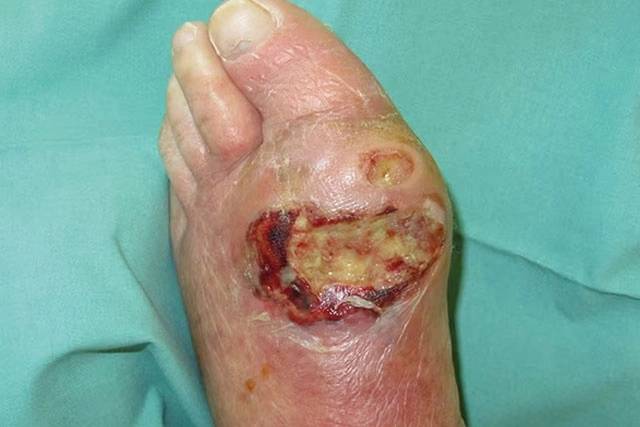

Pie diabético infectado

Ulceras en pie diabético

El pie diabético infectado o con gangrena es una urgencia, acude de forma inmediata a nuestra clínica

• Si tienes una infección y no hay mejoría la herida (presencia de fiebre, escalofríos, hinchazón del pie o pierna, que esta roja la herida, salida de pus).

• Problemas de gangrena (que la herida esta negra, olor fétido).

• Problemas de circulación, que el dedo o dedos estén negros y secos, bordes negros de la herida.

• Ulcera o herida que no cicatriza